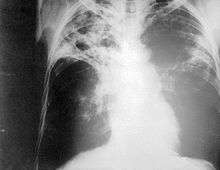

Chest photofluorography

Chest photofluorography, or abreugraphy (also called mass miniature radiography), is a photofluorography technique for mass screening for tuberculosis using a miniature (50 to 100 mm) photograph of the screen of an X-ray fluoroscopy of the thorax, first developed in 1936.